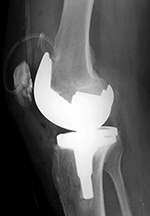

Cruciate retaining total knee arthroplasty (TKA)   Biomet Vanguard 360 Revision Knee System

Cruciate retaining TKA Cruciate retaining TKA Biomet Vanguard 360 knee revision Biomet Vanguard 360 knee revision

68 year-old woman treated for severe left knee osteoarthritis This replaced a loose prior total knee arthroplasty. The patellar button was left in place. A surgical drain is in place, and there is subcutaneous gas from the recent surgery.